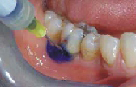

Přístroj na principu světlem aktivovaná desinfekce neboli fotodynamická antimikrobiální chemoterapie. Přístroj s okamžitým účinkem ničí veškeré mikroorganismy bez jakýchkoli vedlejších účinků. Jedná se o bezbolestné ošetření, které nevyžaduje anestezii, nemá vedlejší účinky a ničí 99% bakterií. Používá se především v parodontologii a implantologii při léčbě zánětů v okolí zubů a implantátů (dezinfekce tzv. chobotů), záchovné stomatologii (ošetření kazů) i endodoncii (dezinfekce kanálků zubu).